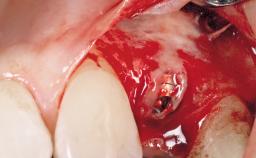

A 30-year-old female patient had lost tooth 21 and was referred to our clinic for consultation and treatment. Due to advanced apical infection, tooth 21 had been extracted two months earlier at another clinic and an acrylic-resin tooth had been bonded to the adjacent teeth. The patient desired implant treatment to avoid any damage to the adjacent natural teeth. While the patient had no history of any systemic disorder, she was a heavy smoker and exhibited medium to advanced periodontitis in the entire jaw. After the initial treatment to achieve a pocket probing depth of less than 4 mm and no bleeding on probing, a decrease in the height of the papillae mesial and distal to the extraction site and overall gingival recession were observed.

Bone Augmentation Horizontal|Staged

Augmentation Materials Autogenous chips|Membrane

Bone Volume Deficient horizontally, requiring prior grafting